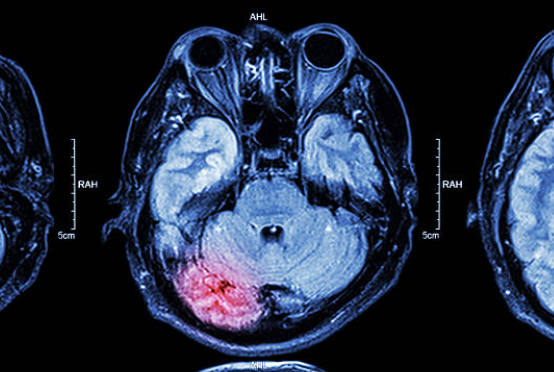

뇌출혈은 뇌혈관이 파열되어 발생하는 심각한 질환으로, 조기 발견과 치료가 매우 중요합니다. 뇌출혈의 전조증상을 인지하는 것은 생명을 구하는 데 큰 도움이 될 수 있습니다. 본 글에서는 뇌출혈의 전조증상, 원인, 예방 방법에 대해 자세히 알아보겠습니다.

뇌출혈의 원인

뇌출혈의 원인은 다양하지만, 주로 고혈압, 혈관 질환, 외상 등이 있습니다. 특히 고혈압은 뇌출혈의 가장 큰 위험 요소로 알려져 있습니다. 고혈압이 지속되면 혈관이 약해지고, 이로 인해 출혈이 발생할 수 있습니다. 그 외에도 다음과 같은 원인이 있습니다.